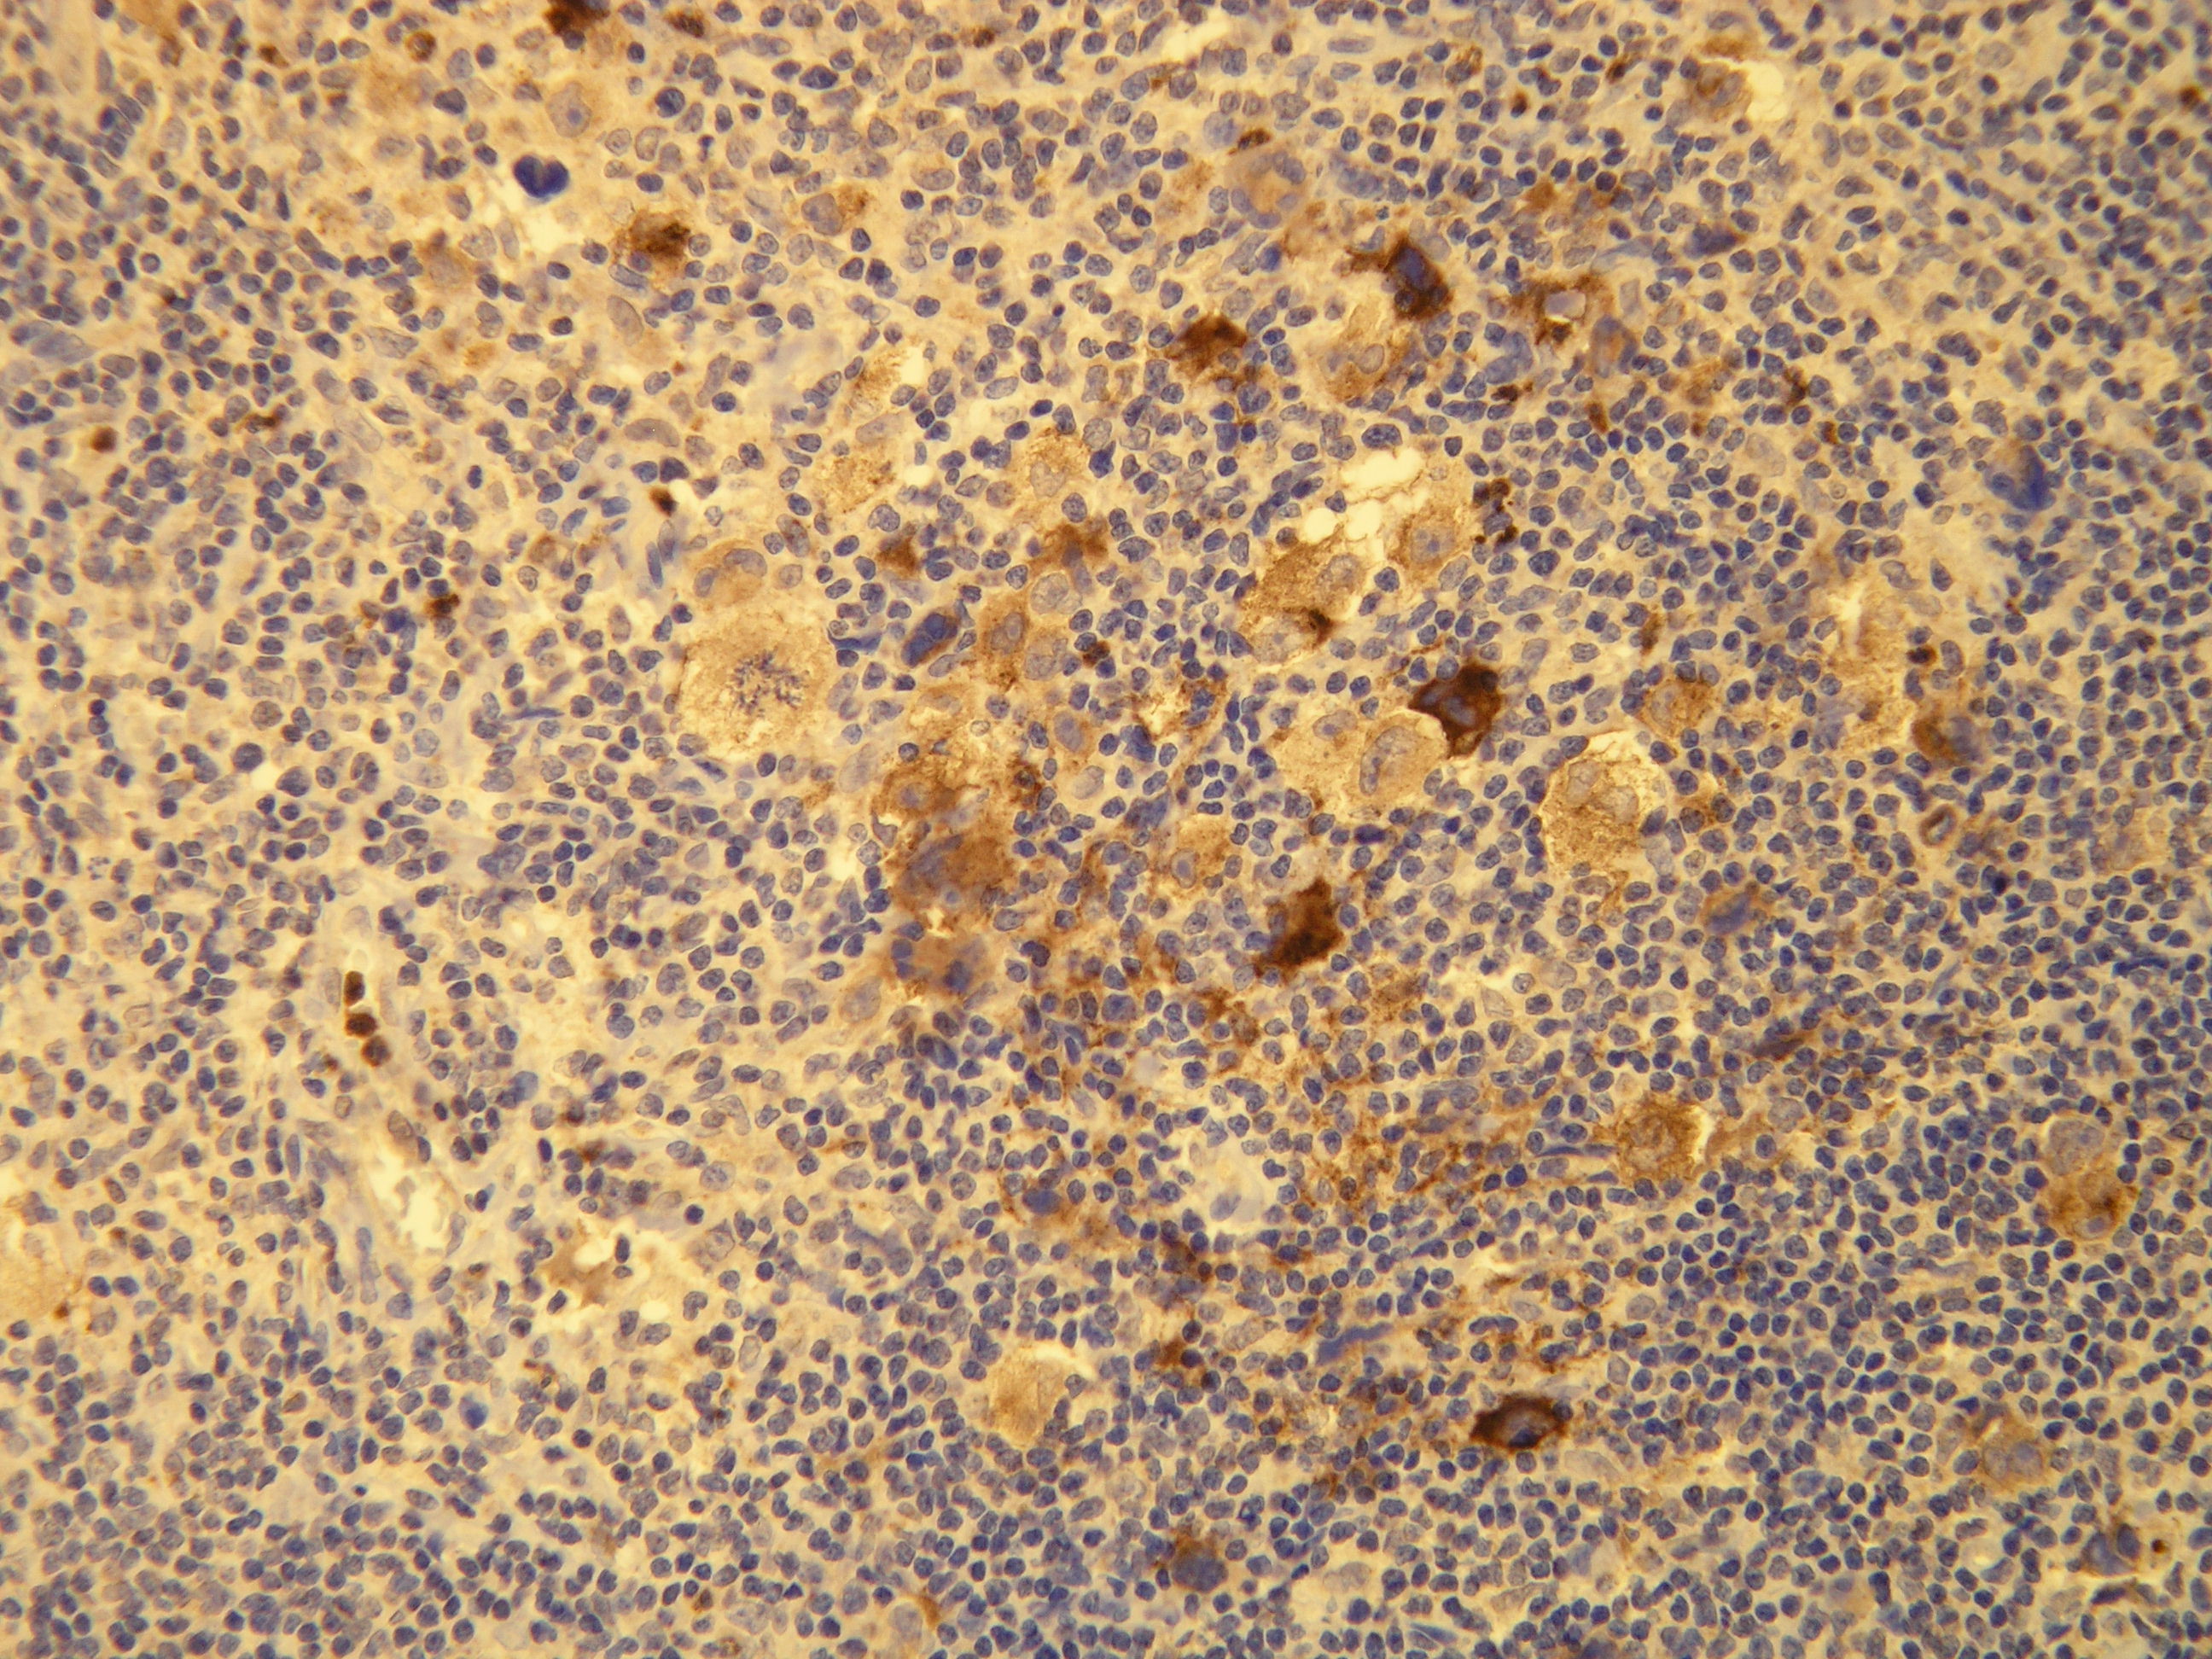

Anti-EBV/LMP-1

IHC-P, riedenie 1:100

db060a